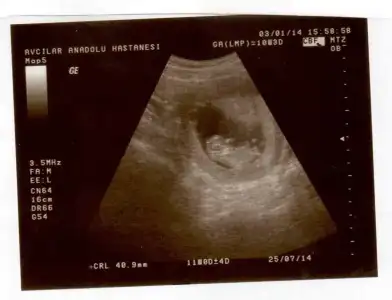

Kızlar benim ilk hamileliğim şu an 8. Haftadayım biliyorum çok çok erken fakat bu topiği takip ediyordum sanki cinsiyeti belliymiş gibi geldi. Anlayanlar bana da yorum yapabilir mi merak ettim :)

Kiz diyim ozaman ben pipisi varsa zatn buyumemistr daha